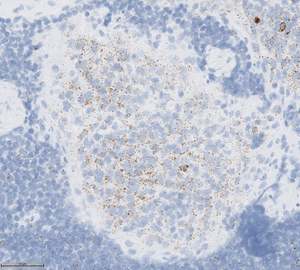

Halpを用いた解析例(fig.2)(fig.3

* ヒト扁桃組織 PPIB染色